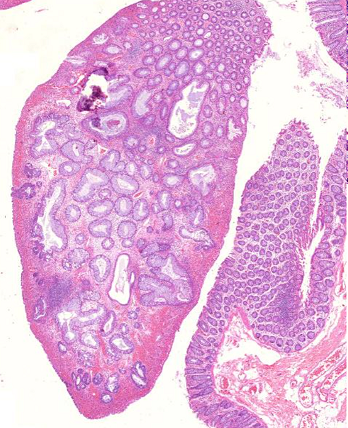

1. Adenoma tubular (A538)

2. Pólipo juvenil (200)